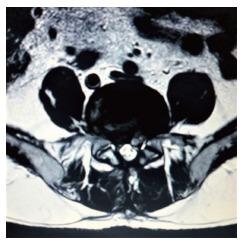

Transforaminal Percutaneous Endoscopic Discectomy (TPED) is a minimally invasive technique mainly used for the treatment of lumbar disc herniation from a lateral approach. Performed under local anesthesia, TPED has been proven to be a safe and effective technique which has been also associated with shorter rehabilitation period, reduced blood loss, trauma, and scar tissue compared to conventional procedures. However, the procedure should be performed by a spine surgeon experienced in the specific technique and capable of recognizing or avoiding various challenging conditions. In this review, pitfalls that a novice surgeon has to be mindful of, are reported and analyzed.

经椎间孔入路经皮内镜下椎间盘切除术(TPED)是一种主要用于从侧方入路治疗腰椎间盘突出症的微创技术。TPED在局部麻醉下进行,已被证明是一种安全有效的技术,与传统手术相比,它还具有康复期短、失血少、创伤小和瘢痕组织少的特点。然而,该手术应由精通该特定技术且能够识别或避免各种具有挑战性情况的脊柱外科医生进行。在本综述中,报告并分析了新手外科医生必须注意的陷阱。